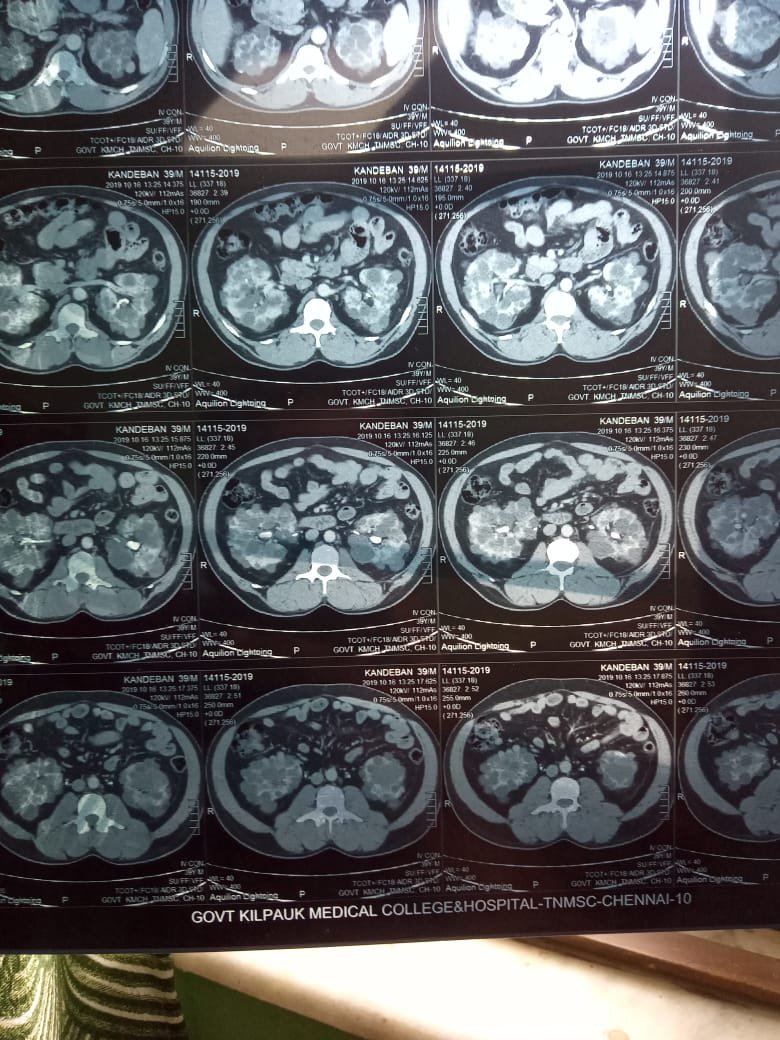

Successfully performed a PCNL for ADPKD, stage 3 CKD with a renal calculus of 5 cm at AG Padmativi Hospital, after two failed attempts in Stanley and MMC Chennai. We did it during the COVID pandemic, thanks to the support and encouragement from our director, Dr. Elangovan sir.